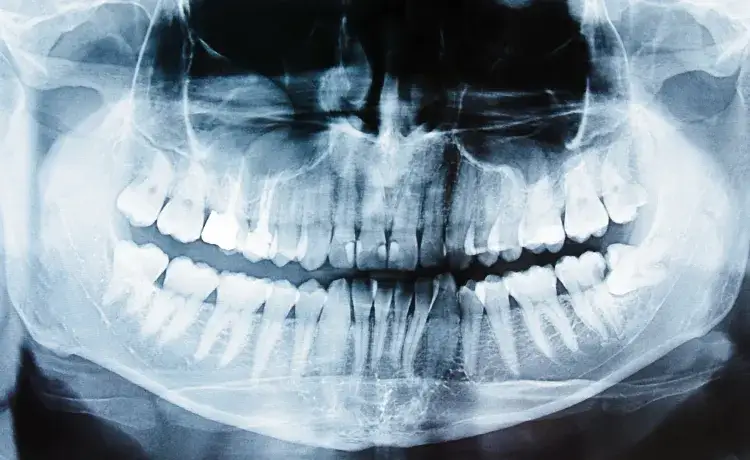

W dobie postępu technologicznego, nowoczesne techniki diagnostyczne stają się kluczowe w leczeniu endodontycznym. Tomografia komputerowa (CT) oraz zdjęcia 3D umożliwiają dentystom dokładne zobrazowanie struktury kanałów, co jest szczególnie przydatne w przypadkach anomalii. Dzięki tym technologiom, lekarze mogą zidentyfikować dodatkowe kanały lub nietypowe kształty, co zwiększa szanse na skuteczne leczenie i minimalizuje ryzyko powikłań.